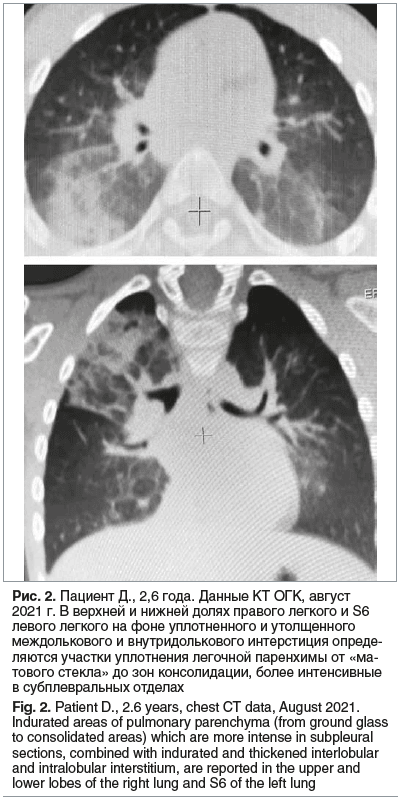

Спустя 3 нед. от последней госпитализации ребенок перенес острый бронхит, вызванный вирусом парагриппа человека 3-го типа (подтвержден лабораторно). Заболевание протекало с фебрильной лихорадкой, одышкой смешанного характера, сильным кашлем. В связи с ухудшением самочувствия пациента, снижением сатурации до 94%, увеличением лабораторной активности (СРБ 25 мг/л), было принято решение об усилении терапии основного заболевания: назначен азитромицин 330 мг/сут в течение 7 дней, а также цефтриаксон 2 г/сут в течение 3 дней. После разрешения бронхита ребенок был выписан домой с рекомендациями продолжить комплексную терапию: иГКС 1000 мкг/сут, ИПВ и азитромицин по схеме (100 мг/сут, 3 раза в неделю) в течение 1 мес. На фоне терапии кашель купировался, подъемов температуры тела больше не отмечалось, самочувствие мальчика улучшилось, одышки не было. На контрольной КТ ОГК через 6 мес. отмечена положительная динамика в виде частичного рассасывания инфильтративных изменений в легких (рис. 2).

На фоне терапии в течение 13 мес. (июль 2021 г. — сентябрь 2022 г.) одышка и кашель купировались, подъемов температуры тела не отмечалось. ОАК, общий анализ мочи, биохимический анализ крови от сентября 2022 г. — без патологических изменений. На КТ ОГК от сентября 2022 г: положительная динамика в виде значительного уменьшения зон консолидации, сохраняется неравномерная воздушность легких, уплотнение легочной ткани по типу «матового стекла».